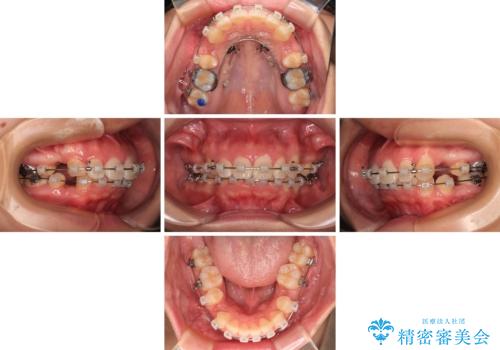

- 矯正装置

- クリアブラケット

また、上顎歯列が下顎に対して前方位に位置していたため、補助装置を用いて上顎歯列を後方に移動させ、より積極的に口元を下げるようにしました。